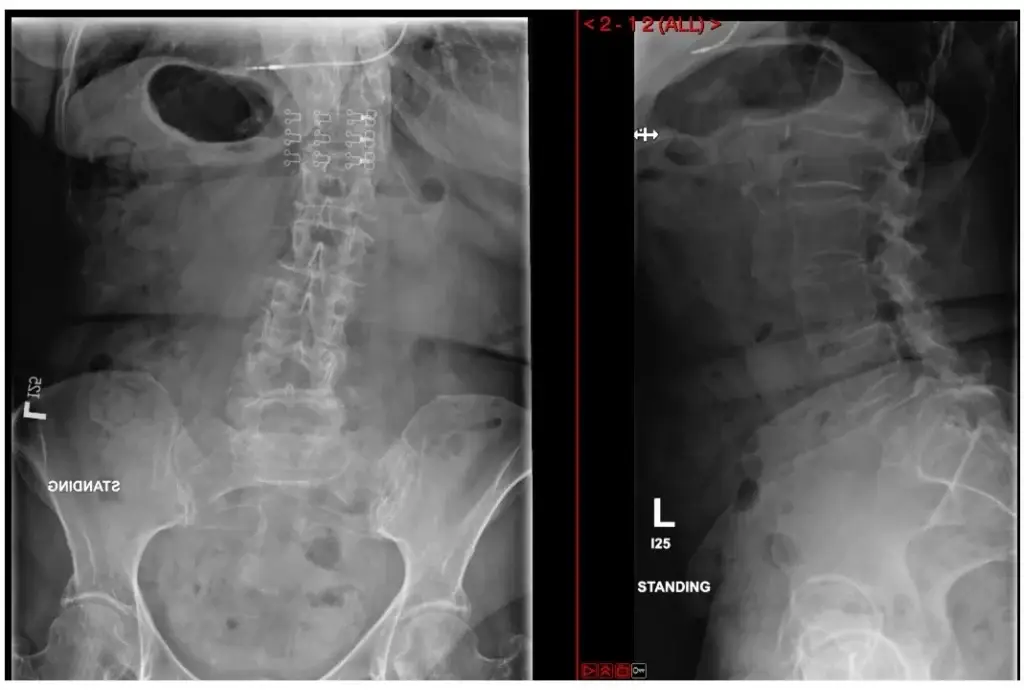

ULBD